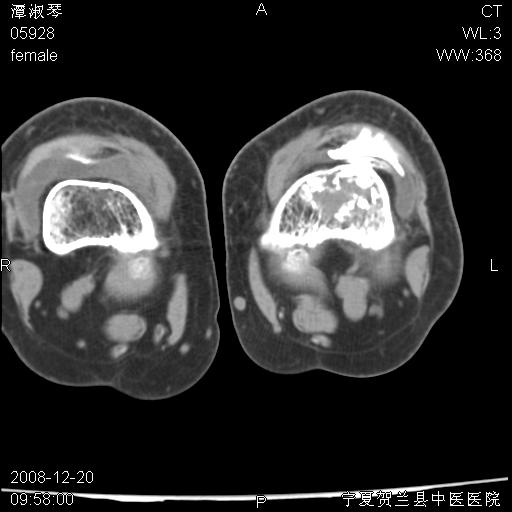

标题: CT17526:请各位看看是啥?

内生软骨瘤?骨梗死?

考虑内生软骨瘤可能性大

考虑-----骨梗死+退变

支持骨梗死,退行性骨关节病,膝关节积液.

考虑骨梗死可能性大

支持骨纤或内生软骨瘤或骨梗死,退行性骨关节病,膝关节积液.

骨梗死可能性大

左股骨下段骨梗死。双膝退变。

支持:内生软骨瘤或骨梗死!另:退行性骨关节病,膝关节积液。

左胫骨下端松质骨及髓腔内可见点片状高密度灶,骨皮质无明显膨胀及变薄。病变范围较长。支持骨梗死,退行性骨关节病,膝关节积液